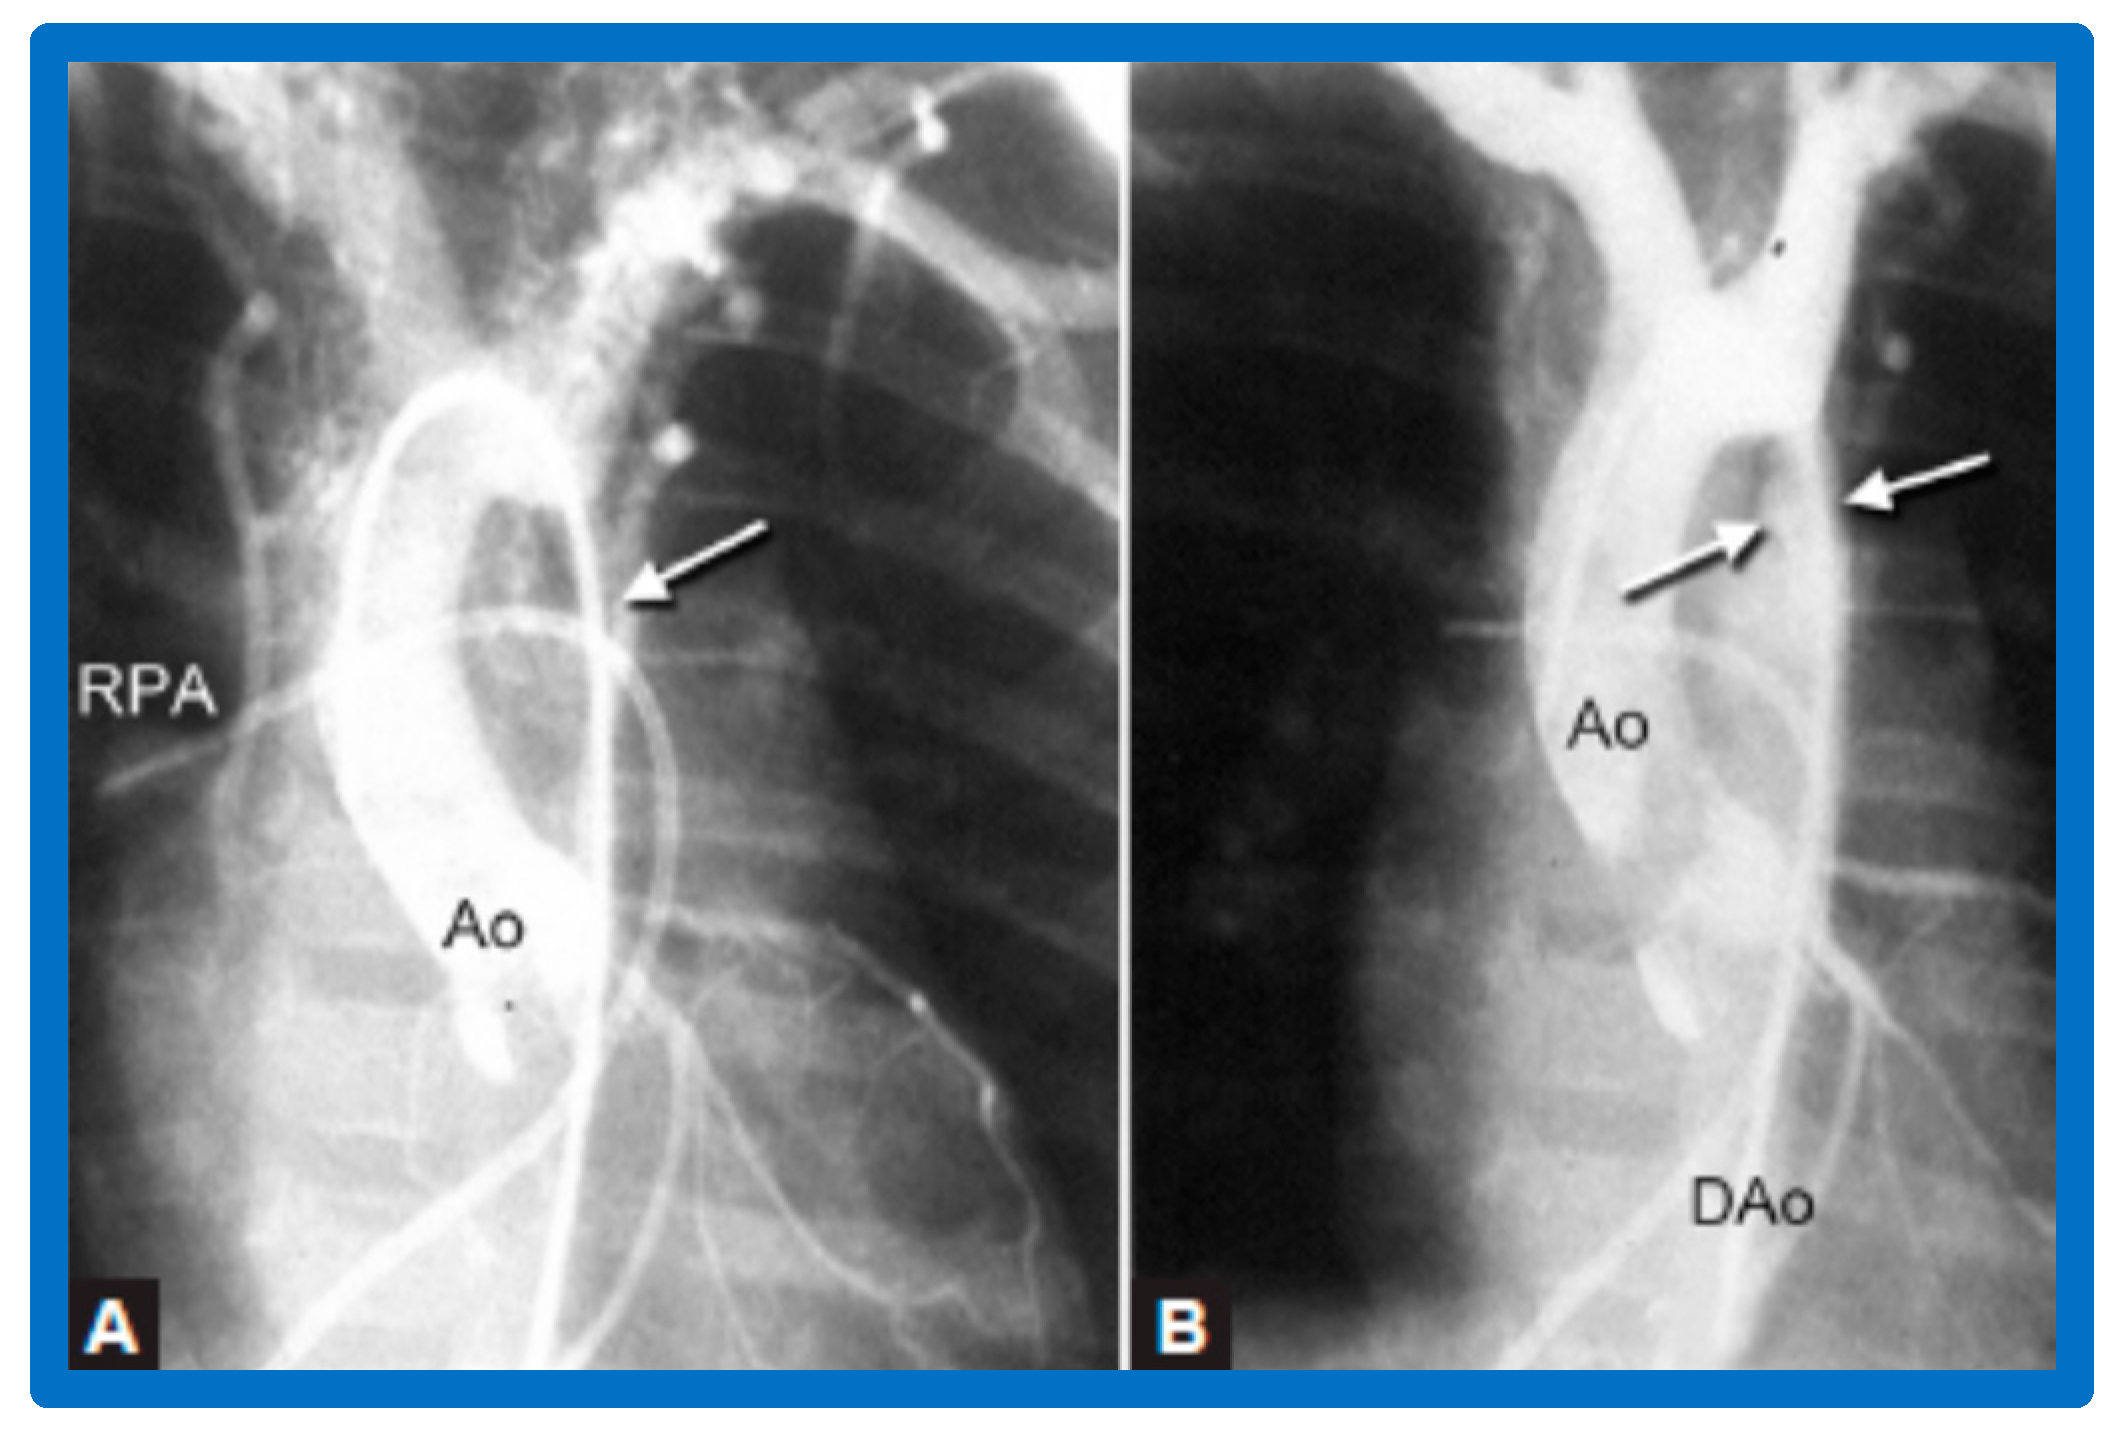

3.1. Pulmonary Stenosis

3.2. Aortic Stenosis

Aortic Stenosis in the Fetus